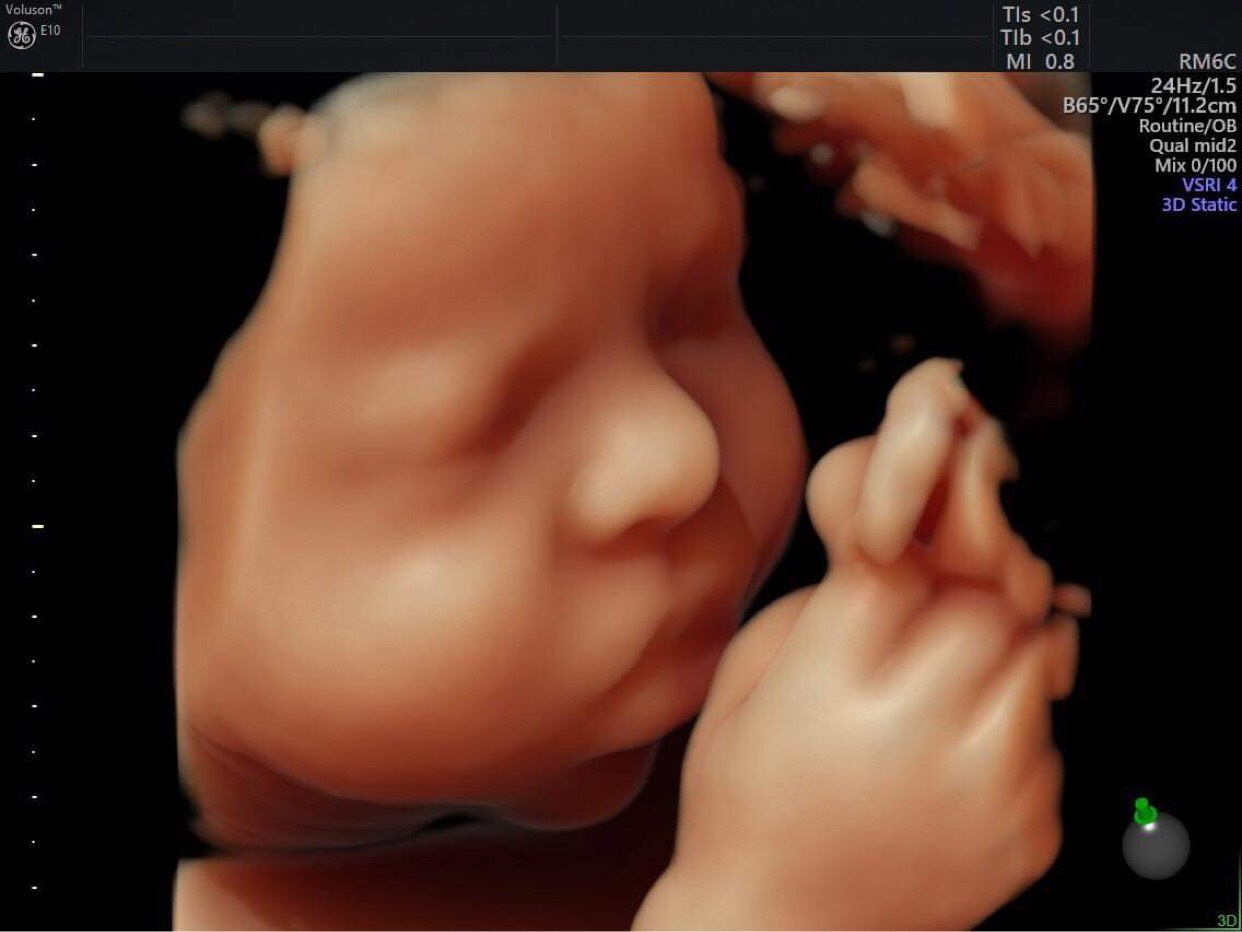

– Ở tuần thứ 31, khi siêu âm, mẹ bầu có thể quan sát thấy rõ sự phát triển của thai nhi: khung xương dần hoàn thiện và cứng cáp hơn, tóc thai nhi bắt đầu mọc, móng tay và móng chân cũng nhú ra. Bé cũng có những cử động nhất định như đạp mẹ, xoay đầu, … và mẹ bầu có thể quan sát những thay đổi đó qua siêu âm Doppler để lựa chọn cách để sinh bé ra dễ dàng hơn.

– Thông qua hình ảnh siêu âm Doppler thai giai đoạn này, mẹ bầu có thể quan sát được cơ thể và khung xương của bé đã phát triển cứng cáp, thay đổi rõ rệt.

– Đồng thời thai nhi cũng có những cử động như chuyển động mí mắt, thai nhi hấp thu được những âm thanh bên ngoài và vì thế sẽ có những phản ứng nhất định thông qua cơ thể.